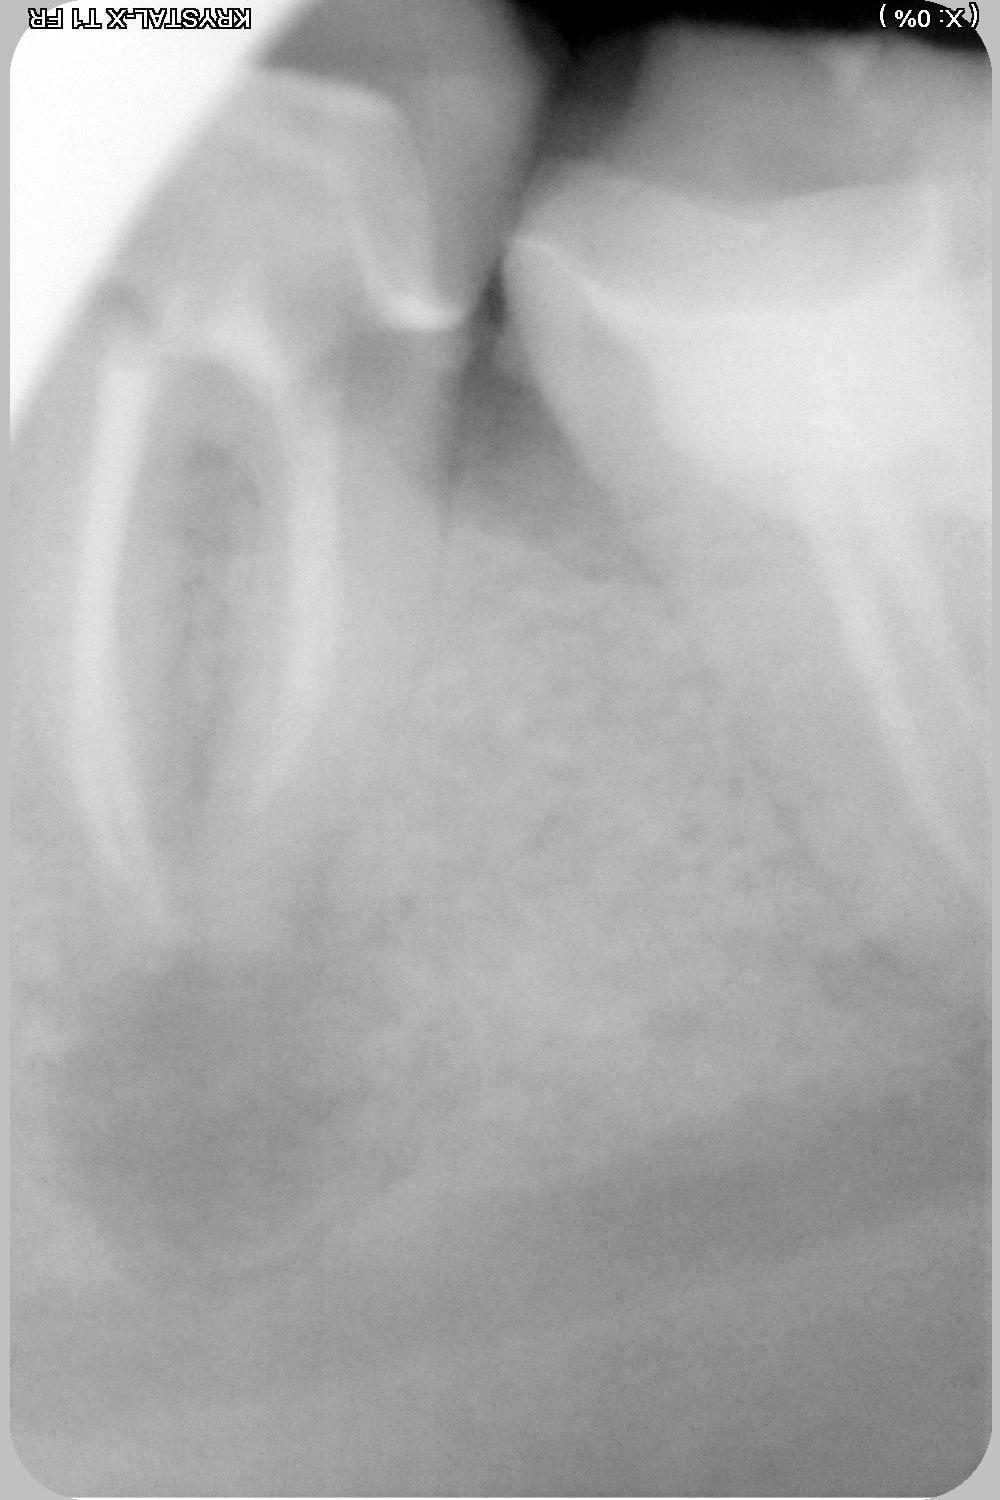

Eh bien je viens d'avoir un patient dont la 37 était obturée avec du compo jusque dans l'entrée des canaux. Je ne vois même pas l'entrée des canaux en vision directe. Il y aurait eu en eugenate au fond j'aurai pris dix fois moins de risque, eucalyptus qui dissout l'eugenate et l'entrée se trouve toute seule. Pas de gutta.